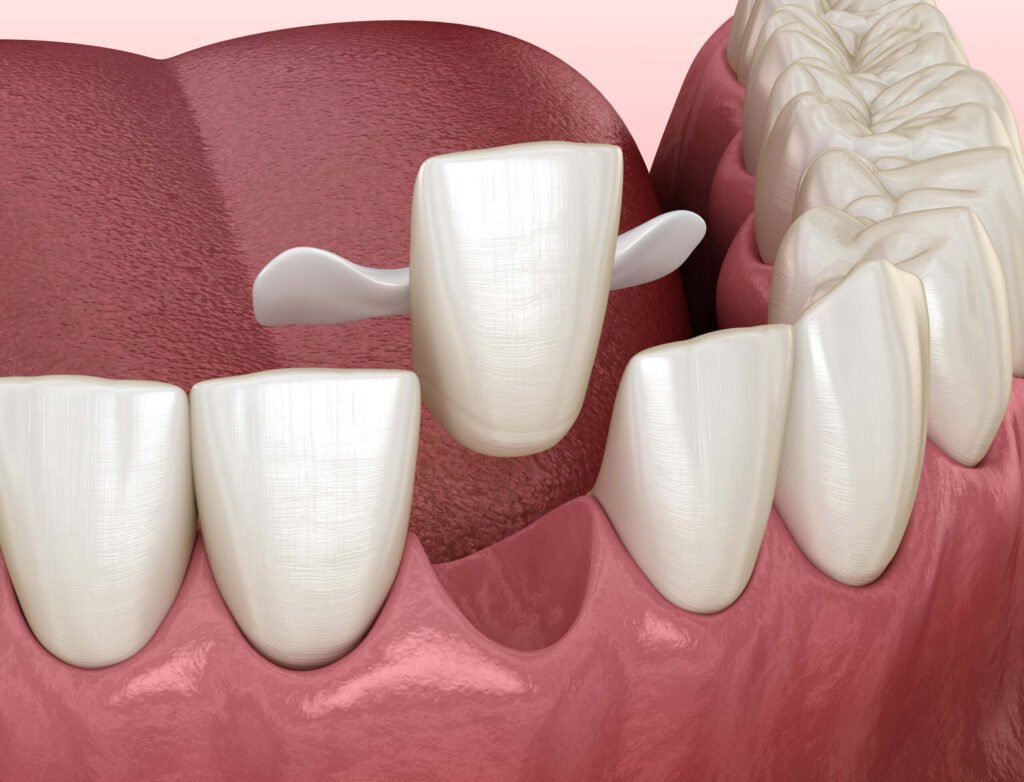

- Bridge fixé ou collé : Une prothèse fixe peut être utilisée pour remplacer les incisives absentes, offrant une solution esthétique et fonctionnelle.

- Considérations socio-économiques : Les bridges antérieurs sont coûteux et complexes à réaliser, avec une fiabilité incertaine. Les bridges collés peuvent être une alternative plus économique.

Les solutions prothétiques, comme les bridges ou les implants, peuvent être coûteuses et nécessitent une maintenance à long terme. Les bridges collés offrent une alternative économique, mais leur fiabilité peut être limitée. Une discussion approfondie avec le patient sur les coûts et les bénéfices à long terme est donc essentielle.